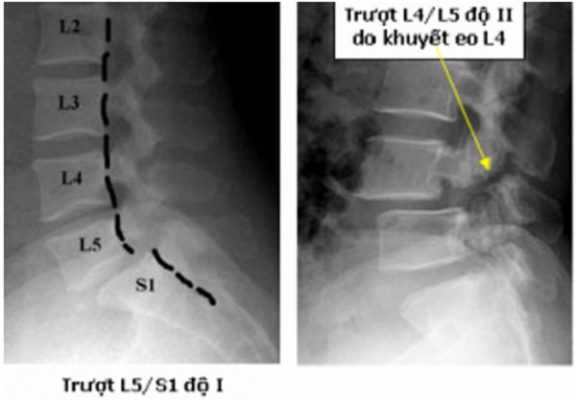

• Các mức độ trượt đốt sống:

– Độ 1: trượt 0 – 25% thân đốt sống.

– Độ 2: trượt 26 – 50% thân đốt sống.

– Độ 3: trượt 51 – 75% thân đốt sống.

– Độ 4: trượt 76 – 100% thân đốt sống.

– Độ 5: trượt hoàn toàn